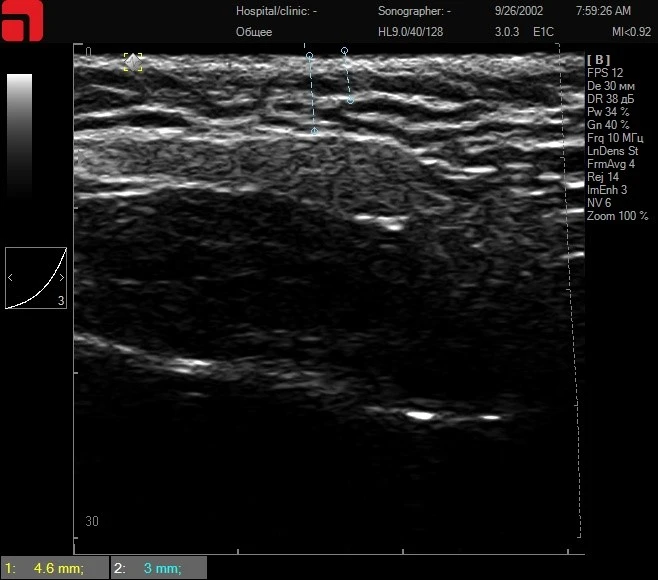

Рис. 2. На сканограмме определяется выраженная соединительная ткань в области подкожно-жировой клетчатки (начинается на глубине от 3 мм), четко дифференцируется соединительная ткань, покрывающая СМАС-слой (глубина 4,6 мм). Противопоказаний к зоне проведения процедуры не выявлено. Основными рабочими датчиками для получения лифтинга будут D4 – 4,5 мм и M7 – 3 мм на аппарате Doublo.

На втором этапе – ультразвуковая диагностика высокого разрешения на аппарате Doublo HIFU. Необходимо просканировать все области, где будет проводиться лечение, определить глубину залегания костных структур, глубоких жировых пакетов, SMAS, подкожно-жировой клетчатки, толщину кожи. Выявить глубину расположения соединительной ткани для подбора датчиков. Также пациента необходимо изучить на предмет возможных противопоказаний к зоне проведения процедуры.